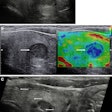

Although breast ultrasound is useful for differentiating masses, the morphologic features of benign and malignant lesions have substantial overlap. Interpretation of these images depends greatly on radiologist experience, leading to the potential for significant interobserver variability, according to the researchers.

As a result, they sought to train a convolutional neural network (CNN) to distinguish between benign and malignant breast masses on ultrasound studies. The researchers retrospectively collected 480 images of 97 benign masses and 467 images of 143 malignant masses for use in training. The deep-learning model, which was developed using the GoogLeNet CNN architecture, was then tested on a set of 120 images of patients with 48 benign masses and 72 malignant masses.